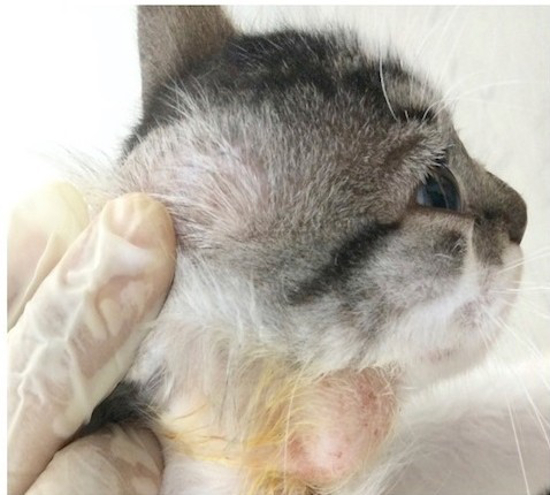

A 6-month-old male feline, mongrel with a history of ingestion of unboiled cow’s milk and after developed signs of anorexia, unproductive cough and lymphadenomegaly. At the physical examination, he had enlargement of mandibular, pre-scapular and popliteal lymph nodes; leukocytosis by neutrophilia on the BCC and in the radiographic examination it was possible to evidence a mixed pulmonary pattern. Additional, cytological and polymerase chain reaction (PCR) tests were performed for a better diagnosis. Then, Ziehl-Neelsen stains were made and we observed a marked amount of bacteria acid type bacilli acid resistant, compatible with Mycobacterium spp. An incisional biopsy of the popliteal lymph node was performed, fixed in 10% formalin for histological processing and immunohistochemistry (IHC). The anti-Mycobacterium spp. antibody was used, checking strong immunostaining in the analyzed tissue. In view of the suspicion of Mycobacterium infection, the combination therapy of 3 antimicrobials (Enrofloxacin 5 mg/kg, clarithromycin 10 mg/kg, and rifampicin 15 mg/kg) was administered orally.

| Figure 1. Enlarged submandibular lymph node in cat |